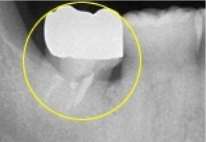

上顎の親知らずを先ほど第2大臼歯を抜歯したところに移植しました。

年齢:57歳

性別:男性

治療期間:6ヵ月

副作用・リスク: 移植は成功率がとても高いですが、お口の中の状態によって変わります。骨の状態によっては出来ない場合があります。